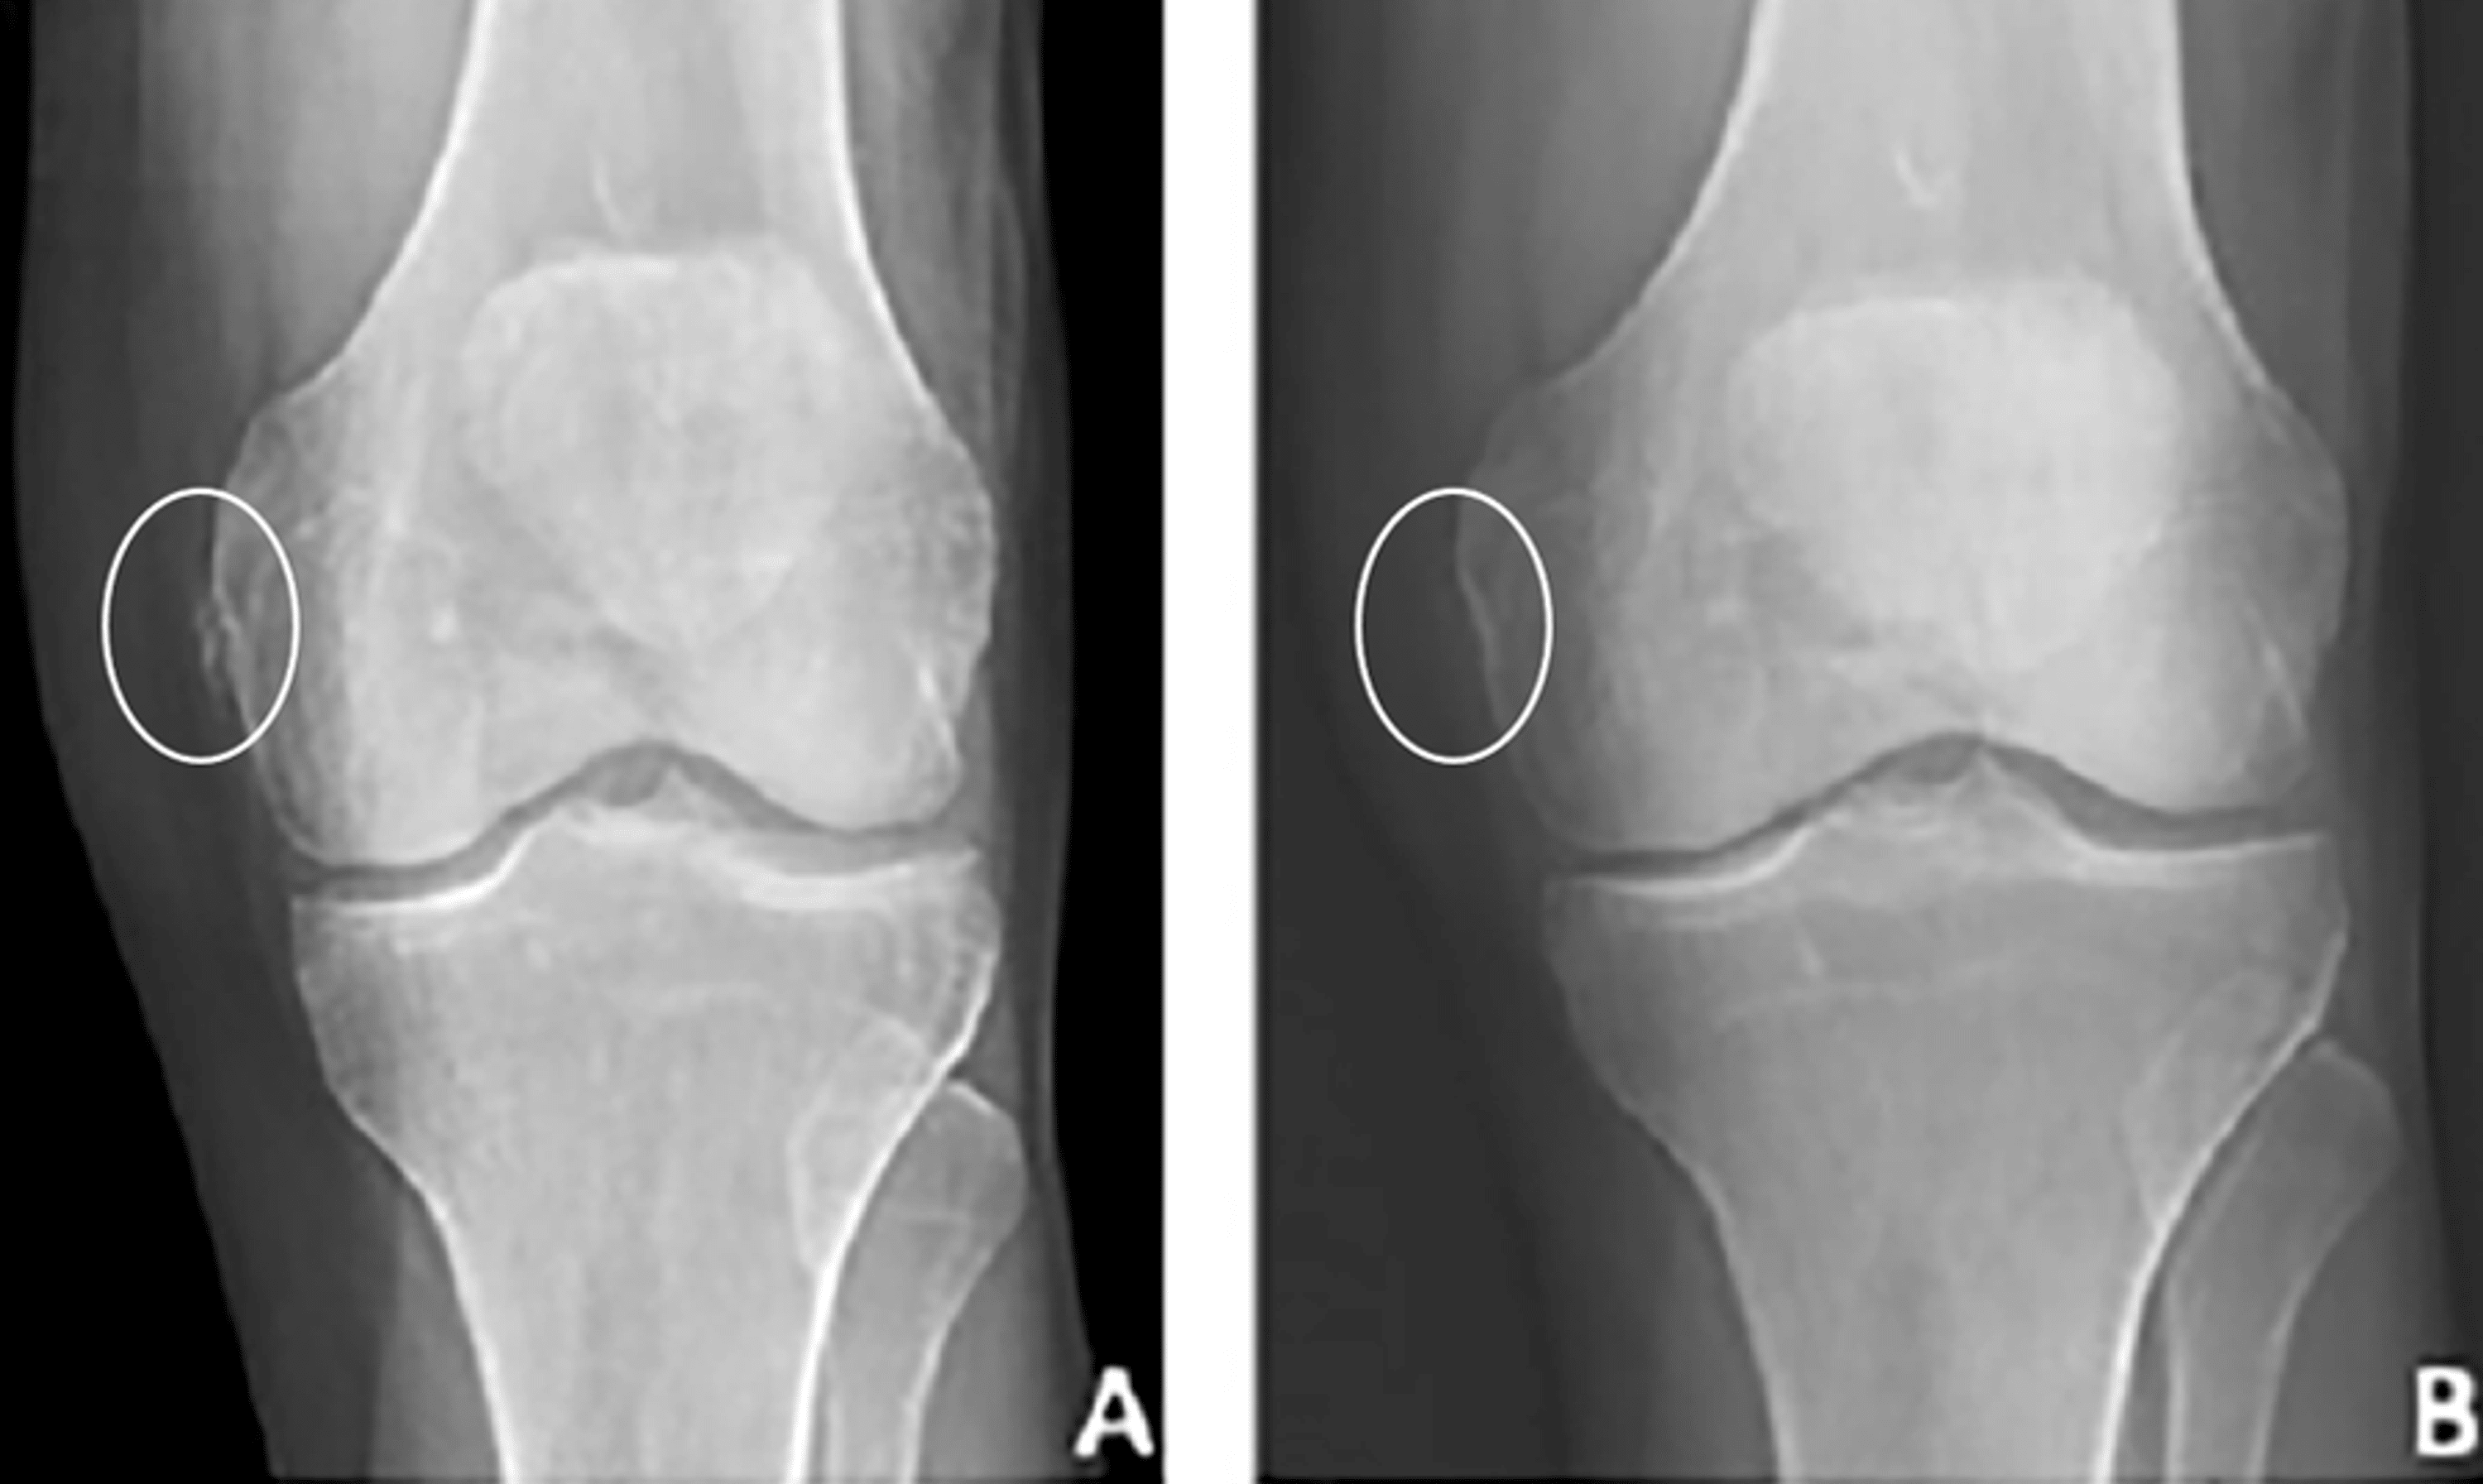

Knee Joint Calcification Radiology . Synovial chondromatosis (osteochondromatosis or synovial chondrometaplasia) also known as reichel syndrome, is a disorder characterized by. Two patterns of calcification are encountered on plain radiographs: Review and correlation with radiographs. Chondrocalcinoses) is a descriptive term indicating the presence of gross calcium deposition within articular cartilage, i.e. Following chemotherapy or radiation therapy, a soft tissue tumor may calcify, due to. Punctate and trabecular/ reticular types (fig. Sagittal ct images of the lumbar spine shows (a) calcium pyrophosphate dehydrate (cppd) crystal deposition (arrowheads in a), (b) hydroxyapatite crystal. There is a wide range of causes of soft tissue calcification 1:. Soft tissue calcification is commonly seen and caused by a wide range of pathology.

Knee Joint Calcification Radiology Two patterns of calcification are encountered on plain radiographs: Synovial chondromatosis (osteochondromatosis or synovial chondrometaplasia) also known as reichel syndrome, is a disorder characterized by. Review and correlation with radiographs. Two patterns of calcification are encountered on plain radiographs: Soft tissue calcification is commonly seen and caused by a wide range of pathology. Chondrocalcinoses) is a descriptive term indicating the presence of gross calcium deposition within articular cartilage, i.e. Following chemotherapy or radiation therapy, a soft tissue tumor may calcify, due to. Sagittal ct images of the lumbar spine shows (a) calcium pyrophosphate dehydrate (cppd) crystal deposition (arrowheads in a), (b) hydroxyapatite crystal. Punctate and trabecular/ reticular types (fig. There is a wide range of causes of soft tissue calcification 1:.

Knee radiograph of knees shows narrowing in joint spaces, subchondral Knee Joint Calcification Radiology Following chemotherapy or radiation therapy, a soft tissue tumor may calcify, due to. Two patterns of calcification are encountered on plain radiographs: Review and correlation with radiographs. Chondrocalcinoses) is a descriptive term indicating the presence of gross calcium deposition within articular cartilage, i.e. There is a wide range of causes of soft tissue calcification 1:. Punctate and trabecular/ reticular types. Knee Joint Calcification Radiology.